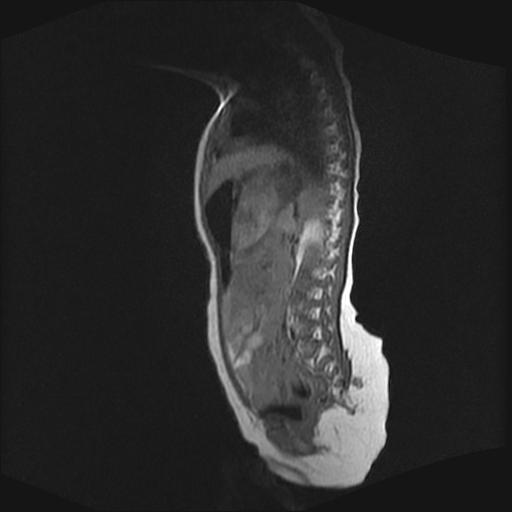

四个月的女婴,ct示脊膜膨出.

脊柱裂、脊膜膨出,请结合临床除外皮毛窦。

脂肪脊髓脊膜膨出

脊柱裂、脊膜膨出